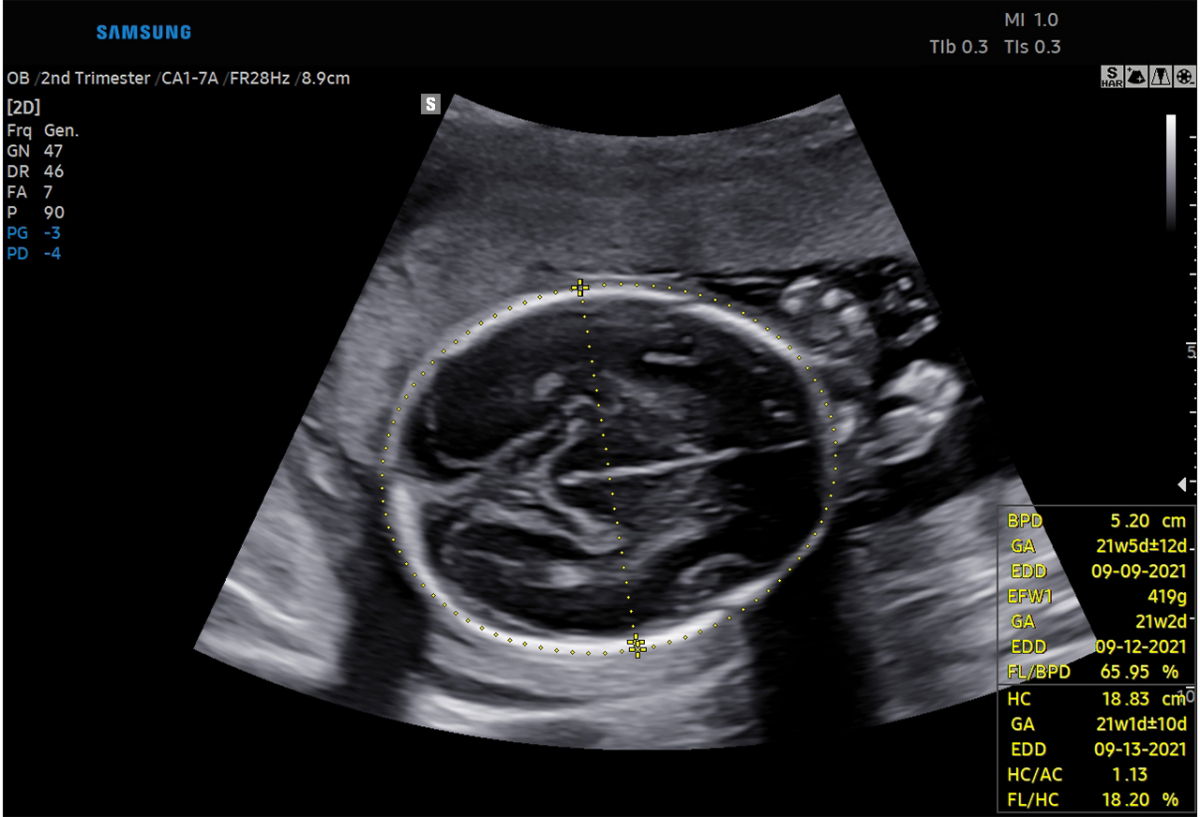

태아의 성장과 발육 상태를 빠르게 판단할 수 있는 ‘바이오메트리’와 태아의 심장 진단을 도와주는 ‘태아심장’ 솔루션이 대표적이다.

‘바이오메트리’ 솔루션은 태아의 영상에서 머리, 배, 다리 등을 인식해 태아의 성장 정도를 측정해주며, ‘태아심장’ 솔루션은 태아의 심장을 인식해 각 부위를 표시하고 측정해주는 기능을 구현한다.